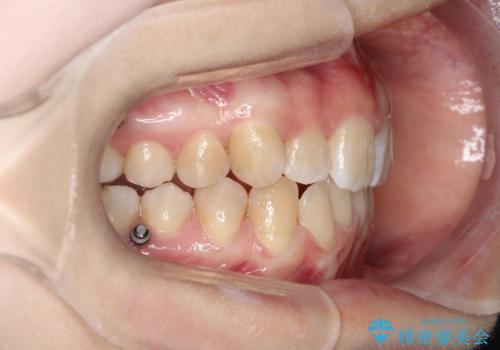

- 前歯のデコボコ(叢生)と、前歯が上下逆の咬み合わせ(反対咬合)を主訴にご来院されました。精密検査の結果、歯列全体のスペースが不足していることが判明。患者様のご希望に合わせ、透明で目立ちにくい**インビザライン(マウスピース矯正)**による治療計画を立案しました。歯を抜かずに、歯列全体を奥(遠心)へ移動させることで、歯が並ぶスペースを確保し、叢生と反対咬合を同時に改善することを目指します。

今回の矯正治療では、透明なマウスピース型の装置インビザラインを使用しました。この装置は目立たず、取り外しが可能なため、食事や歯磨きも普段通り行えます。治療は、緻密な治療計画に基づき、段階的に作製されたマウスピースを交換していくことで、遠心移動という方法で奥歯から徐々に歯列全体を後方へ動かしました。これにより、不足していたスペースを確保し、前歯のデコボコを解消。同時に、上下の歯の前後的な関係を改善することで、反対咬合も正常な咬み合わせへと導きました。見た目も機能も改善し、自然で美しい笑顔を獲得していただけました。